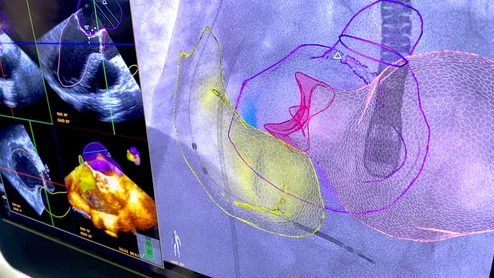

The pressure is on for ASE and other societies to create a new CPT code for the use of interventional echocardiography during structural heart procedures.